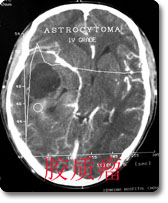

中枢神经影像诊断是本科室的特色、强项诊断之一,尤其是现代影像学诊断,如CT、MRI等,是西南地区最早开展此项工作的单位,积累了丰富的临床经验,有较高的诊断水平。如对脑肿瘤的影像学表现和肿瘤分子生物学基础的对照研究、脑血管病的诊断和介入治疗等在国内处于领先地位。 |